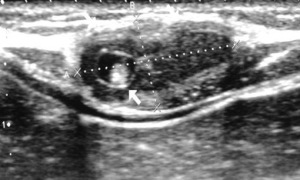

| Фото. Цистицеркоз глаз: А Киста цистицерка под конъюнктивой в наружном углу глаза; Б цистицерк на глазном дне, вертикальная стрелка указывает место выхода паразита через сосуды сетчатки поврежден пигментный эпителий сетчатки, горизонтальная стрелка указывает на отслойку сетчатки вокруг цистицерка, белое пятно в центре кисты это сколекс паразита; В На УЗИ цистицерк на глазном дне киста (толстая стрелка) и сколекс (тонкая стрелка) паразита. | ||

Цистицеркоз диагностируют при помощи УЗИ, рентгена, КТ, МРТ и биопсии. На УЗИ хорошо видно кисту и сколекс цистицерка в мышцах и подкожной клетчатке. На рентгене видно кальцификаты. КТ и МРТ полезны для определения точного расположения цистицерка. На КТ лучше видны мелкие кальцинаты. На МРТ лучше видно сколекс и кисту.